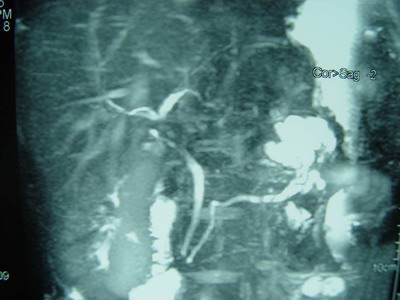

MRCP